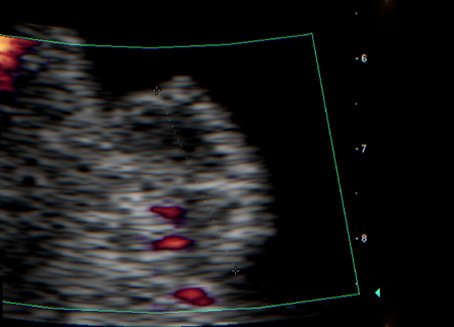

Ultraschallaufnahme Harnblasentumor

Wir bieten für Medizinstudenten ab dem 5. Semester sowie interessierte Assistenz- und Fachärzte einen Ultraschallkurs nach individueller Vereinbarung für zwei bis sechs Teilnehmer an. Nach kurzer theoretischer Einführung zur Sonografie, Dopplersonografie und zur Anwendung von Ultraschallkontrastmitteln werden zunächst ca. 100 Ultraschallsequenzen (kurze Videoclips) von Normal- und pathologischen Befunden demonstriert und nachfolgend gegenseitige Untersuchungen bzw. Untersuchungen an Patienten mit typischen urologischen Befunden durchgeführt.